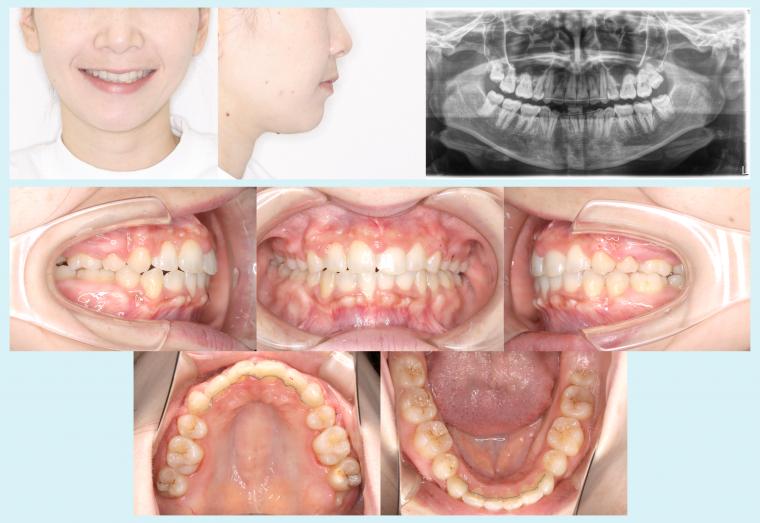

#51 矯正用インプラントアンカーを用いてオートローテーションを図った症例